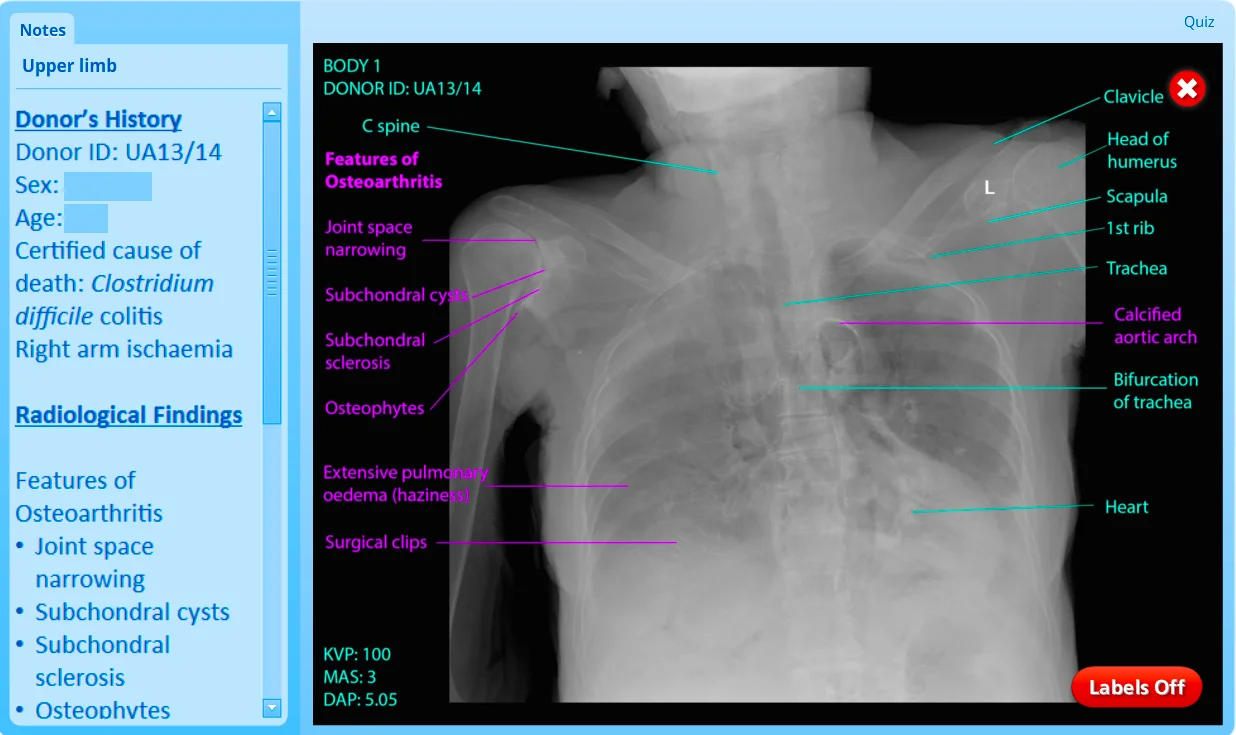

Screenshots of X-perience Interface

Using Adobe Photoshop (Adobe, United States) the identity was removed from each image and the images were systemically labelled. Collaborating with consultant radiologists in Mount Sinai Hospital, New York and in the Mater Misercordiae Hospital, Dublin the images were systematically labelled with both anatomical and pathological findings. This made the images clinically relevant for students as well as a valuable study tool for anatomy. Khalil et al. stress the importance of clear labelling to empower rather than overwhelm the student [6]. Clinical histories were researched from donor files and presented alongside the images to provide a comprehensive profile on each donor.

The body region of interest could be chosen by clicking on the body outline or by clicking on the tabs. Factual information was presented alongside the images of interest, briefly describing topics such as intramembranous and endochondral ossification, fracture classification and treatment options. On viewing a specific image, students were initially presented with an unlabelled image, which allowed feature discovery by the student. Labels pointing out relevant anatomical structures in green and pathological findings in pink could be turned on as desired. The radiological findings relevant to the specific image could be seen alongside the image in a side bar.